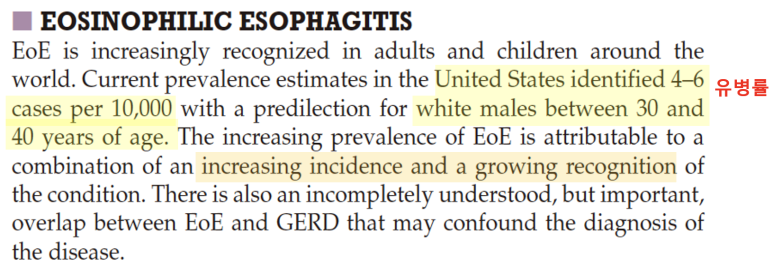

일반적으로 식도와 관련된 증상이 있어 내시경을 받는 환자 중 7% 가까이 호산구 식도염의 빈도가 보고되며 삼키기 곤란, 음식물 관련 증상이 동반되는 환자 중에서는 호산구 식도염의 빈도가 23%-50%까지 올라갈 수 있다고 보고하였습니다. 그러나 중요한 점은 증상과 식도의 조직학적 소견이 반드시 일치하는 것은 아니기 때문에 증상만으로 진단이나 치료경과를 판단하지 않는다는 점을 강조하고 있습니다.역학 호산구 식도염 유병률은 미국 기준 1만명당 4~6명이며, 주로 30~40대 백인 남성으로 밝혀지고 있습니다. 최근 호산구 식도염 유병률이 증가하는 이유는 호산구 발생 자체의 증가와 함께 인식의 증가가 복합적으로 작용하고 있다고 보고하고 있습니다.

한편, 유럽에서는 10만명 당 13-49명 발생한다고 보고하고 있으며, 주로 30-50세 사이의 성인 남성에게 자주 발생한다고 보고하고 있습니다.진단방법으로는 바륨스터디를 시행하는데, 비특이적이며 내시경 소견이 중요합니다.